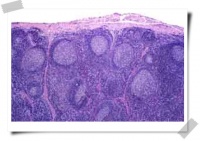

淋巴结:49号切片,牛淋巴结,HE染色

淋巴结HE染色图

(1).被膜:由较致密的结缔组织构成,被膜伸入淋巴结内,形成小梁。

(2).皮质:

淋巴小结:在被膜下方,圆形或卵圆形。在淋巴小结内可看到三种结构:帽区、亮区、暗区。

高倍显微镜下淋巴结HE染色图

皮质淋巴窦:被膜下或小梁旁,以及与淋巴小结之间,窦壁由内皮细胞组成,靠被膜或小梁侧窦壁完整;有网状细胞的突起在皮质淋巴窦中形成网眼,网眼中有少量淋巴细胞。巨噬细胞 。

副皮质区:位于淋巴小结和髓质之间,有大量散在淋巴细胞,主要是T淋巴细胞,还有巨噬细胞。

(3).髓质:即位于淋巴结的中央部分,由髓索和髓质淋巴窦组成。

髓索:淋巴组织排列成索状,与副皮质区相连。髓索内有淋巴细胞,浆细胞,巨噬细胞等。

髓质淋巴窦:夹于髓索之间,与皮质淋巴窦相通,结构也相同、巨噬细胞。